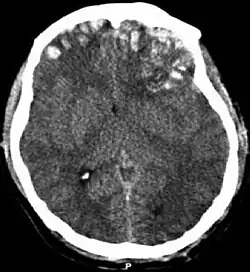

![]() Obraz tomografii komputerowej pokazujący stłuczenie mózgu, krwiak śródczaszkowy, i podtwardówkowy oraz złamanie czaszki[1]. | |